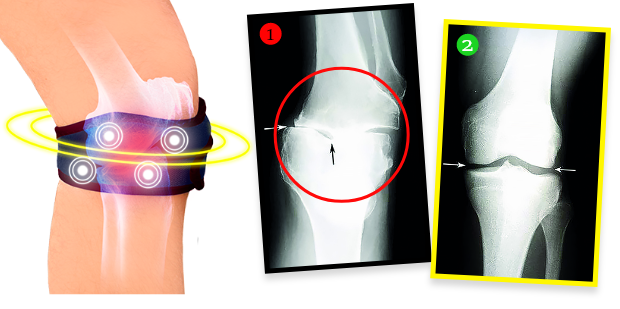

4 FASI D’AZIONE della ginocchiera biomagnetica antidolore e rigenerante:

- Elimina dolore e rigidità articolare già entro le prime 72 ore di utilizzo

- Scarica e stabilizza le articolazioni, accelerando la rigenerazione della cartilagine e la ricostruzione del liquido sinoviale

- Riduce la tensione muscolare, rigenera i tessuti e rafforza le strutture articolari dall’interno, invertendo i cambiamenti degenerativi

- Attenua gonfiori e infiammazioni, eliminando in modo duraturo la fonte del dolore

La signora Elena, dopo la terapia, ha fatto una radiografia ed è risultato che le degenerazioni del ginocchio erano completamente regredite! Il medico è rimasto senza parole – non sapeva cosa dire. I fatti sono che, grazie alla ginocchiera biomagnetica, la condizione del ginocchio non solo non è peggiorata, ma la cartilagine e le strutture delicate dell’articolazione si sono rigenerate, riportando il ginocchio alla piena efficienza di anni fa. La ginocchiera emette infatti un campo biomagnetico naturale e sicuro che penetra nei tessuti più profondi dell’articolazione, nutrendo e rigenerando la cartilagine, restituendole elasticità e resistenza, e stimolando la produzione del liquido sinoviale che ammortizza e protegge dal doloroso sfregamento nei movimenti. È una terapia completamente non invasiva e sicura.